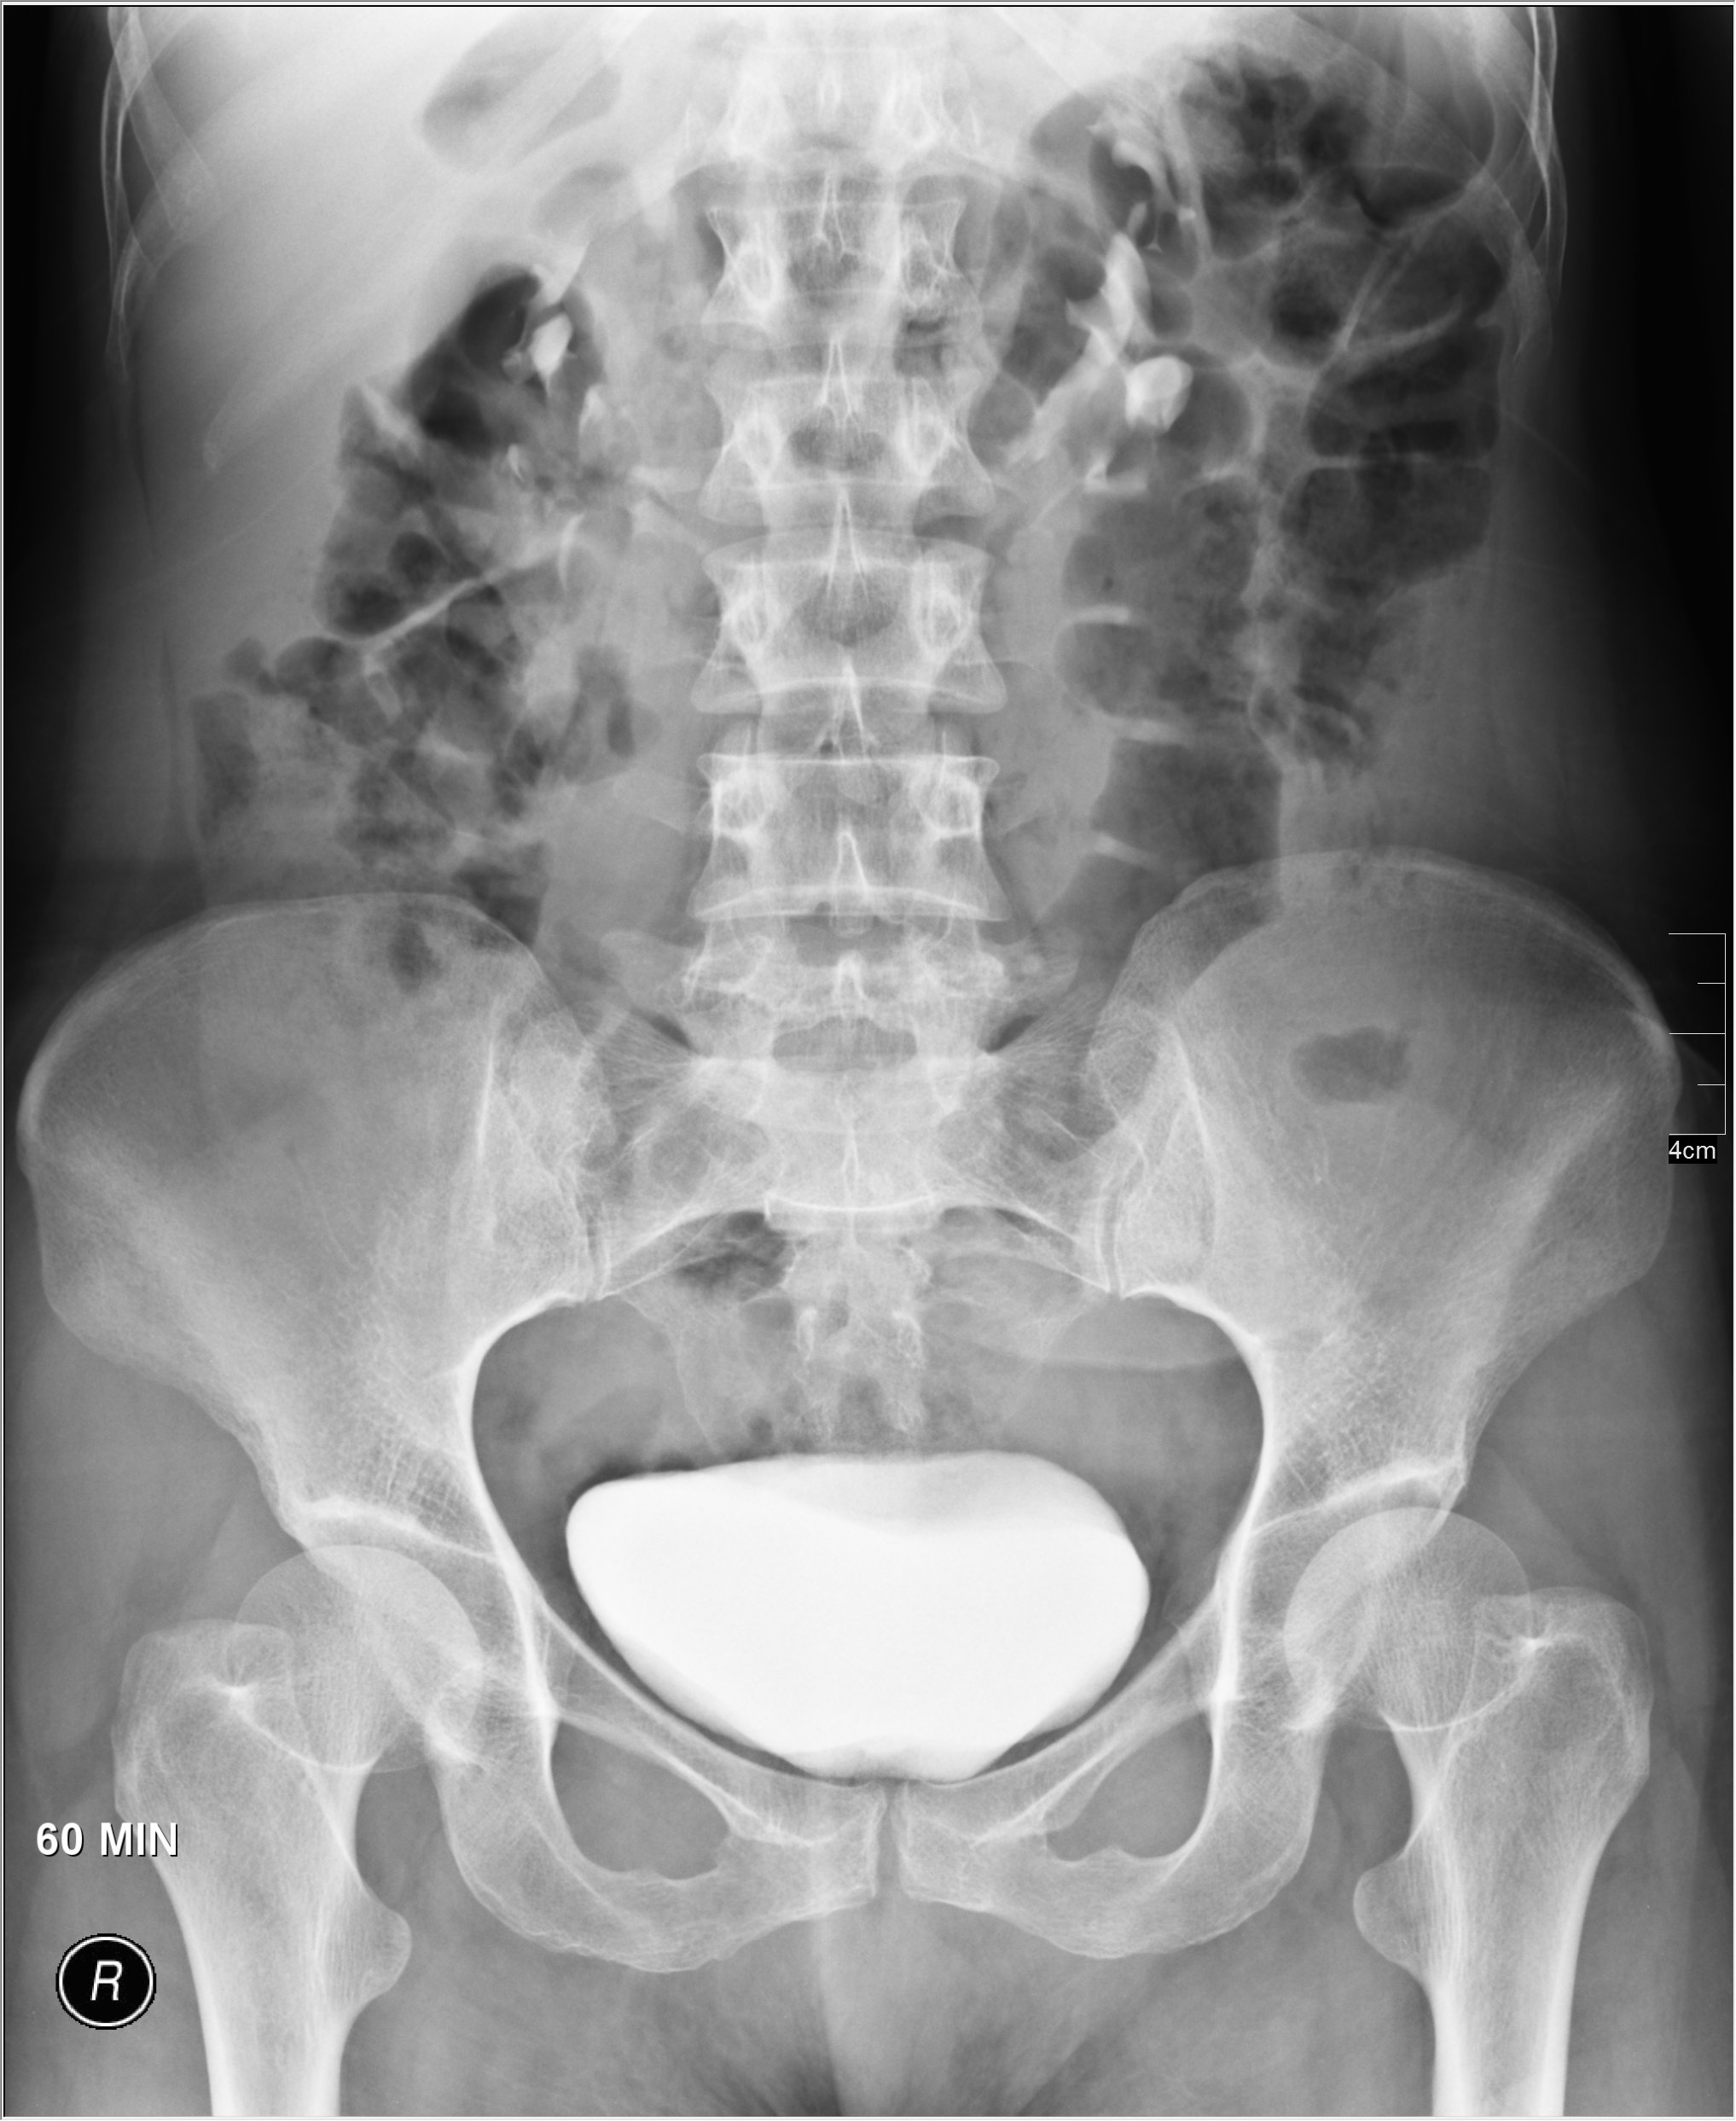

Медицинские изображения и примеры эксреторной цистографии